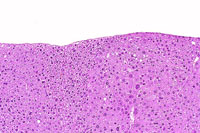

A basophilic adenoma. Basophilic adenomas are often comprised of closely spaced hepatocytes with small amounts of cytoplasm.

A basophilic adenoma.